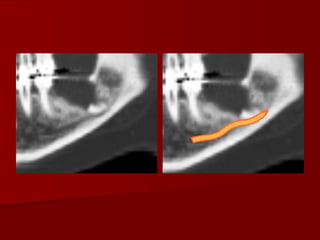

Imaging of Lingual Nerve Injuries CT

Imaging of LingualNerve Injuries CT